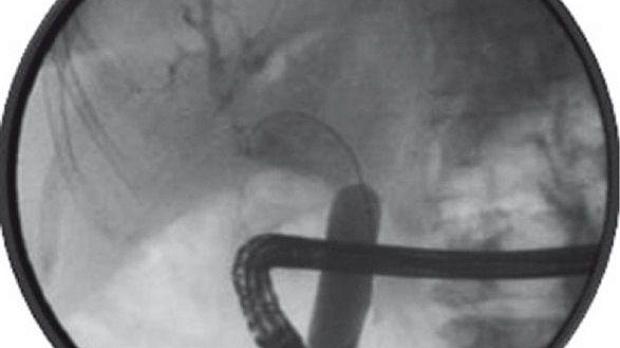

Классификация перфораций двенадцатиперстной кишки, связанных с выполнением эндоскопических транспапиллярных вмешательств, и лечебная тактика по Stapfer M, 2000

Тип

Локализация и описание

Причина

Рекомендованная тактика лечения

1

Перфорация латеральной или медиальной стенки кишки, обычно больших раз­меров, расположена далеко от БСДК

Травма эндоскопом

Экстренная операция

II

Изолированное околососоч- ковое повреждение

ЭПСТ

Обычно консер­вативное лечение

III

Повреждение дистальной части желчного протока, обычно небольших размеров

Перфорация проводником или корзиной Дормиа

Обычно консервативное лечение

IV

Наличие пневморетропери- тонеума (без четких призна­ков повреждения стенки)

Избыточная ин- суфляция воздуха в просвет кишки

Консервативное лечение

Примечание: БСДК - большой сосочек двенадцатиперстной кишки; ЭПСТ - эндоскопическая папиллосфинктеротомия

Stapfer M., Selby R.R., Stain S.C., et al. Management of duodenal perforation after endoscopic retrograde cholangiopancreatography and

sphincterotomy // Ann. Surg. – 2000. – Vol. 232. – P. 191–198.